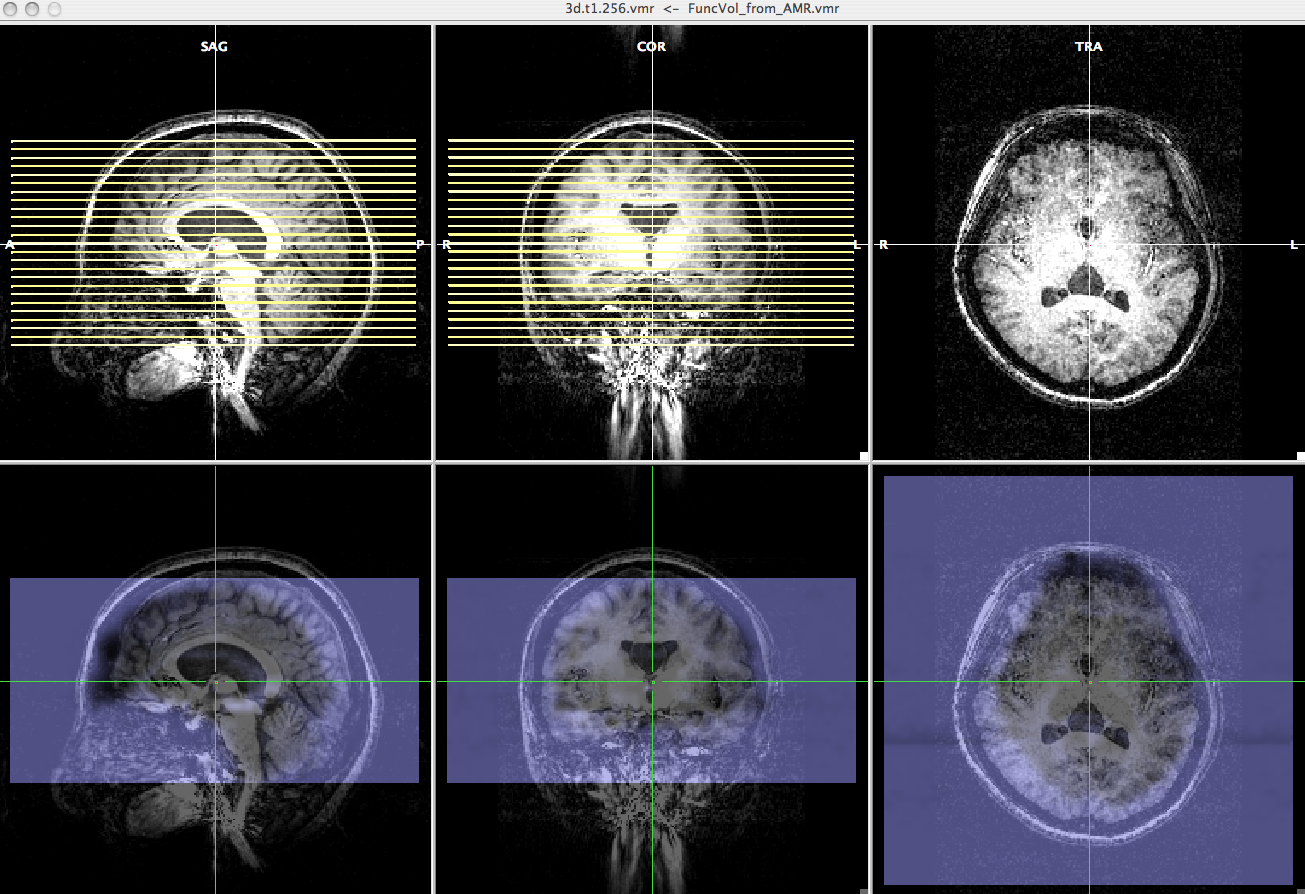

- On the "3D Volume Tools" dialogue, choose "Spatial Transf" and press "Show VTC Vol" and after a while, you will see the image aligned epi image.

- Click the "Blend2" and you can check if the epi image are correctly aligned to anatomy image.